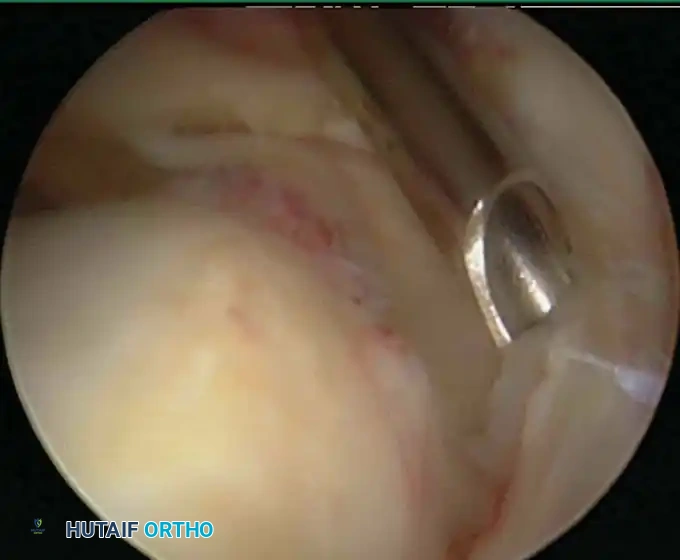

Modern arthroscopy relies heavily on suture anchors (biocomposite or all-suture constructs) and advanced arthroscopic knot-tying or knotless techniques. The ability to pass sutures through retracted, fibrotic tissue and secure them under appropriate tension without strangulating the microvascular supply is the hallmark of a master arthroscopist.

* Debridement/Acromioplasty: Immediate passive and active-assisted range of motion to prevent adhesive capsulitis.

* Rotator Cuff Repairs: A phased approach beginning with 4 to 6 weeks of strict passive motion to protect the healing tendon-to-bone interface, followed by active-assisted motion, and finally, progressive resistance strengthening at 10 to 12 weeks.